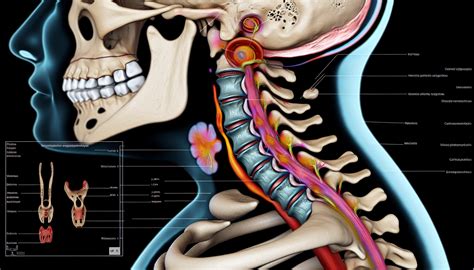

Understanding a Bulging Disc in Neck

A bulging disc in the neck is a common spinal condition that can cause significant discomfort and pain. The cervical spine, which consists of seven vertebrae in the neck, supports the head and allows for a range of motion. Each vertebra is separated by a disc that acts as a shock absorber and provides flexibility. When a disc bulges, it can press on nearby nerves, leading to various symptoms.

Diagnosing a Bulging Disc in Neck

• Imaging tests: Ordering diagnostic tests such as X-rays, MRI, or CT scans to visualize the spine and identify the bulging disc.